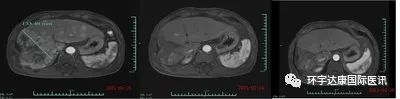

值得一提的是,受试者 007 肿瘤体积在细胞治疗输注后一个月减少了 80% 以上!受试者 012 也看到了良好的肿瘤反应,他患有晚期和弥漫性大块 HCC,并在放疗、靶向药物和 12 次 TACE 失败后加入该研究。在 CAR-T 细胞输注后第 28 天,靶肿瘤病灶的直径从基线时的 133 毫米减小到 9 毫米,减少了 93% 以上。目前,受试者正在接受 CAR-T 细胞输注后第 3 个月的评估,MRI 扫描显示肿瘤几乎完全消退!